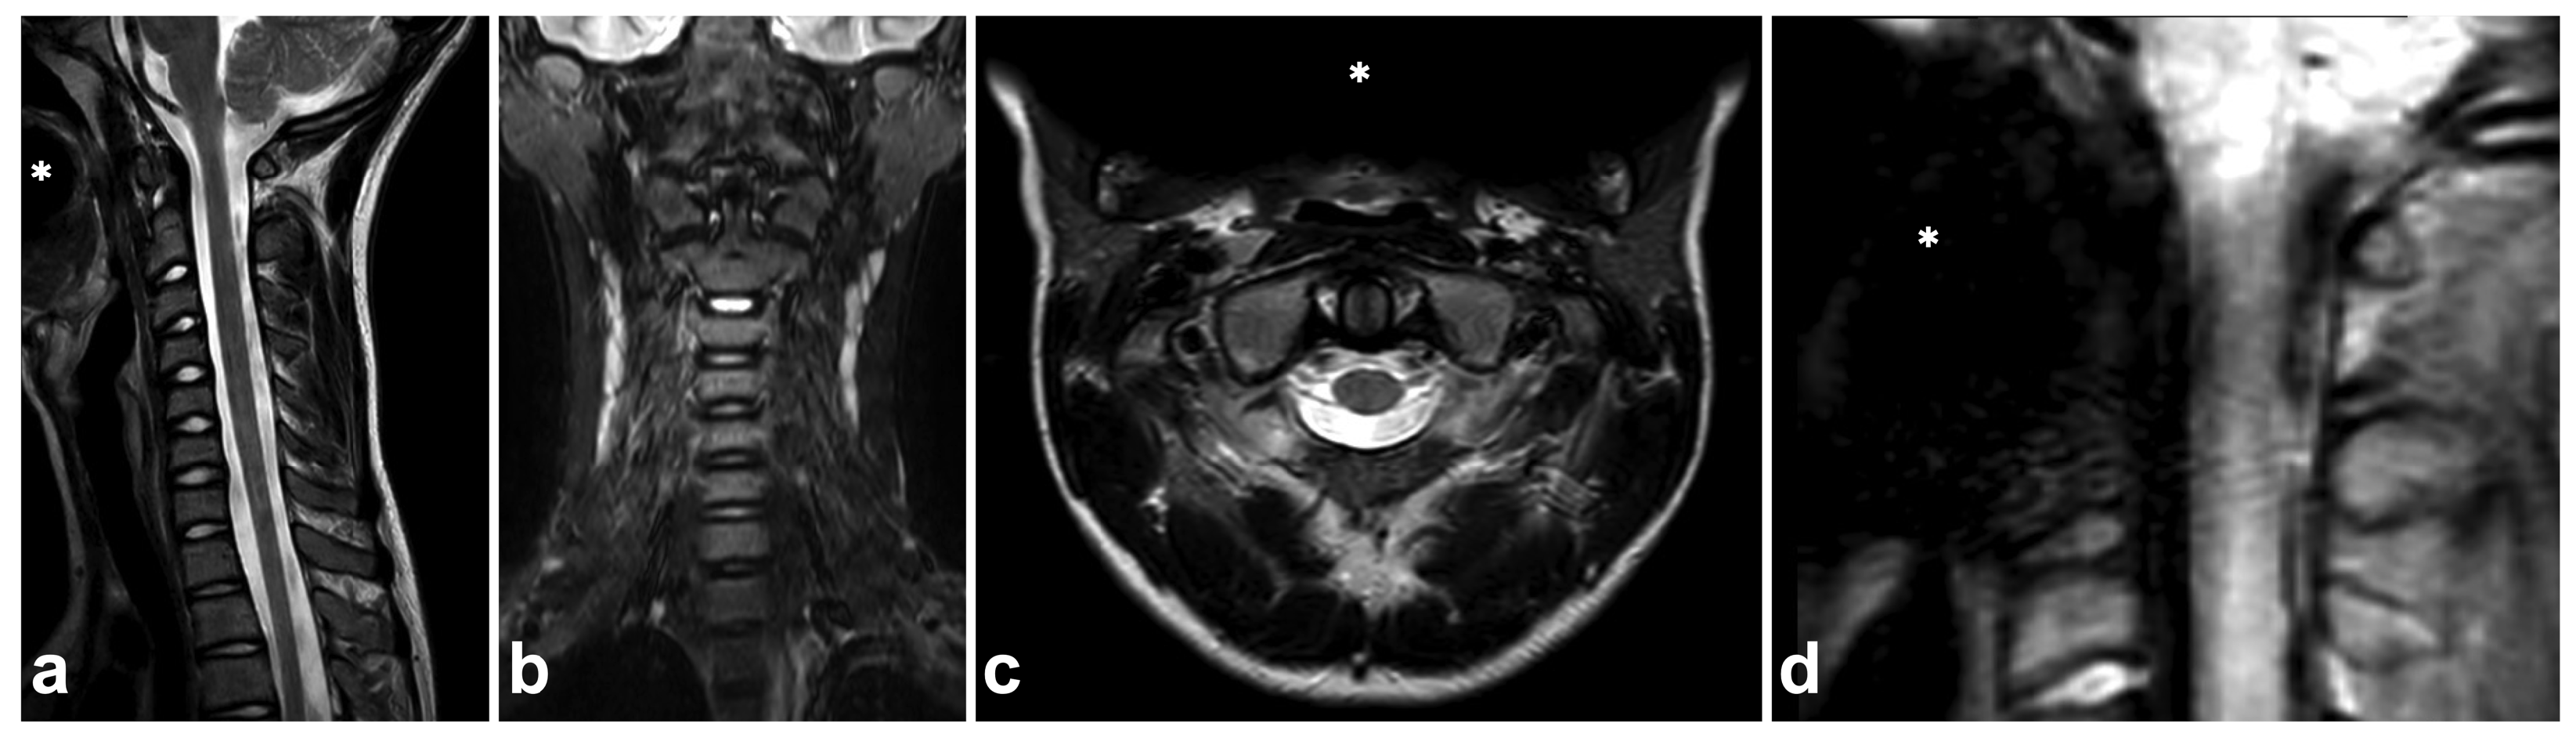

6. Spinal Cord Injuries